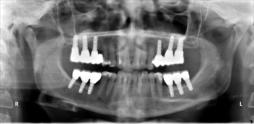

Beispiele für komplexe implantologische Versorgungen aus unserer Gemeinschaftspraxis

(Planung / Endversorgung -- als Röntgenaufnahmen)

C1

C2

C3